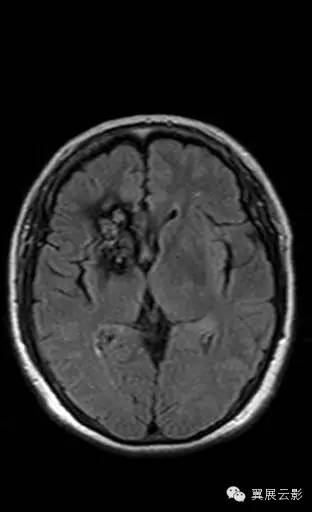

右侧基底节区可见不规则团片状混杂信号灶,累及右侧侧脑室前角,大小约15×34mm,边界尚清,呈爆米花样改变,T1WI等高信号,T2WI/FLAIR呈混杂稍高信号,边缘可见低信号环,无明显占位效应,DWI低信号。

海绵状血管瘤由扩张、衬有内皮的窦样间隙构成,窦样间隙排列紧密,无正常脑组织间隔,病变呈圆形或分叶状,几乎百分之百有瘤内出血。约80%发生于幕上,最常见于额、颞叶深部髓质区、皮髓质交界区和基底节区,也可发生于小脑、脑干和脊髓,约50%病例多发。CT平扫表现为一边缘清楚的圆形或类圆形高密度病灶,密度可均匀不一,常无灶周水肿,无或仅轻度占位征象。合并出血时,病灶可短时间内增大,出现明显占位征象,常伴钙化,增强扫描可有轻度至明显强化。MRI表现不一,取决于出血和时期,急性较大的出血可能掩盖海绵状血管瘤的典型特征,网状的“爆米花”样病变是最特征性的表现,中心呈混杂信号,周边有完整的含铁血黄素环。病灶内含有不同阶段的出血是信号不均匀的原因,在SWI中显示尤为清楚,常有多发低信号灶。